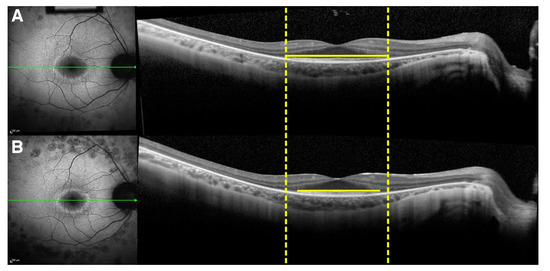

The external boundary of the hyperautofluorescent ring was manually measured by its horizontal and vertical diameters using the measuring tool provided in the Spectralis software (Figure 6). In cases in which a complete ring was not seen, only the observable axis was measured. The external edge of the ring was preferred over the internal edge owing to its greater definition and distinct appearance, allowing for more precise measurements. The interest in studying photoreceptor survival led to the decision to measure the EZ line width due its reliability, as opposed to the interdigitation zone (IZ) line, which cannot always be distinguished, even in normal subjects [30]; the EZ line is readily detectable in every patient. The EZ width was manually measured on the high-resolution horizontal scan through the fovea using the measuring tool in the Spectralis software (Figure 7).

Figure 6.

Progression of hyperautofluorescent ring diameters seen in short-wavelength autofluorescence (SW-AF) imaging of a patient with retinitis pigmentosa (RP). (A) A SW-AF scan of a hyperautofluorescent ring in RP at the baseline visit. Dashed yellow lines are tangential to the horizontal-most edges of the hyperautofluorescent ring. Green lines span the vertical diameter of the ring, while yellow lines span the horizontal diameter. The horizontal diameter of the ring is noticeably larger at the baseline visit than at the follow-up (B).